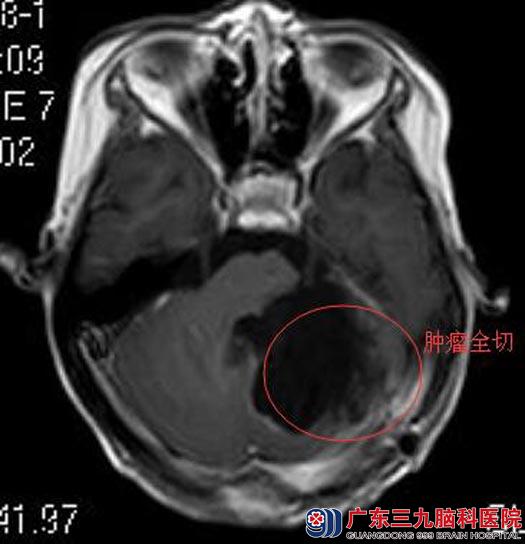

前一日凌晨,小雨再次出现恶心、呕吐,精神差。她的父母明白:髓母细胞瘤是最常见的儿童原发恶性脑肿瘤,是中枢神经系统恶性程度最高的神经上皮性肿瘤之一,严重威胁儿童生命和生存质量。连夜将小雨送到广东三九脑科医院综合神经外科,头颅MR检查提示:左侧小脑半球病灶范围较前明显增大,其内新增出血,强化范围较前明显扩大,周围水肿较前加重,邻近硬脑膜强化范围较前扩大,肿瘤呈扩展趋势。一直担心的事还是发生了:“肿瘤复发!”

“我该怎么办?”小雨的妈妈迫切地想给女儿最好的治疗。经过讨论,决定荧光导航下切除复发肿瘤。由鲁明主任主刀,在全麻下行左侧小脑半球复发髓母细胞瘤切除术,皮层下见黄白色肿瘤组织,质软,其间夹带黑褐色血凝块,予清除血块,荧光导航下将肿瘤全切。术后小雨神志清醒,未再出现呕吐。术后病理结果:黑色素髓母细胞瘤IV级。